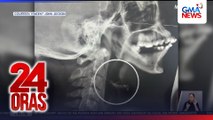

Aksidente naman sa Pagbilao, Quezon. Dalawa ang patay at mahigit 30 ang sugatan matapos mahulog ang sinasakyan nilang bus sa bangin.

01:46Ayon sa pagbilaw MDR-RMO, 37 ang sakay ng bus,

01:50kabilang ang konduktor at driver.

01:52Dalawang nasawik sa trahedya.

01:55Isinugod naman sa ospital ang mga sugatan.